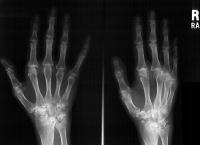

Clinical Example: Rheumatoid arthritis with DRUJ and radiocarpal involvement

Rheumatoid arthritis has many forms of presentation. This patient has bilateral severe radiocarpal and distal radioulnar joint involvement, with relative sparing of the metacarpophalangeal and interphalangeal joints.

The radiolunate joint did not spontaneously fuse on this side, allowing a greater degree of ulnar translation of the carpus. Note the severe cystic carpal changes.